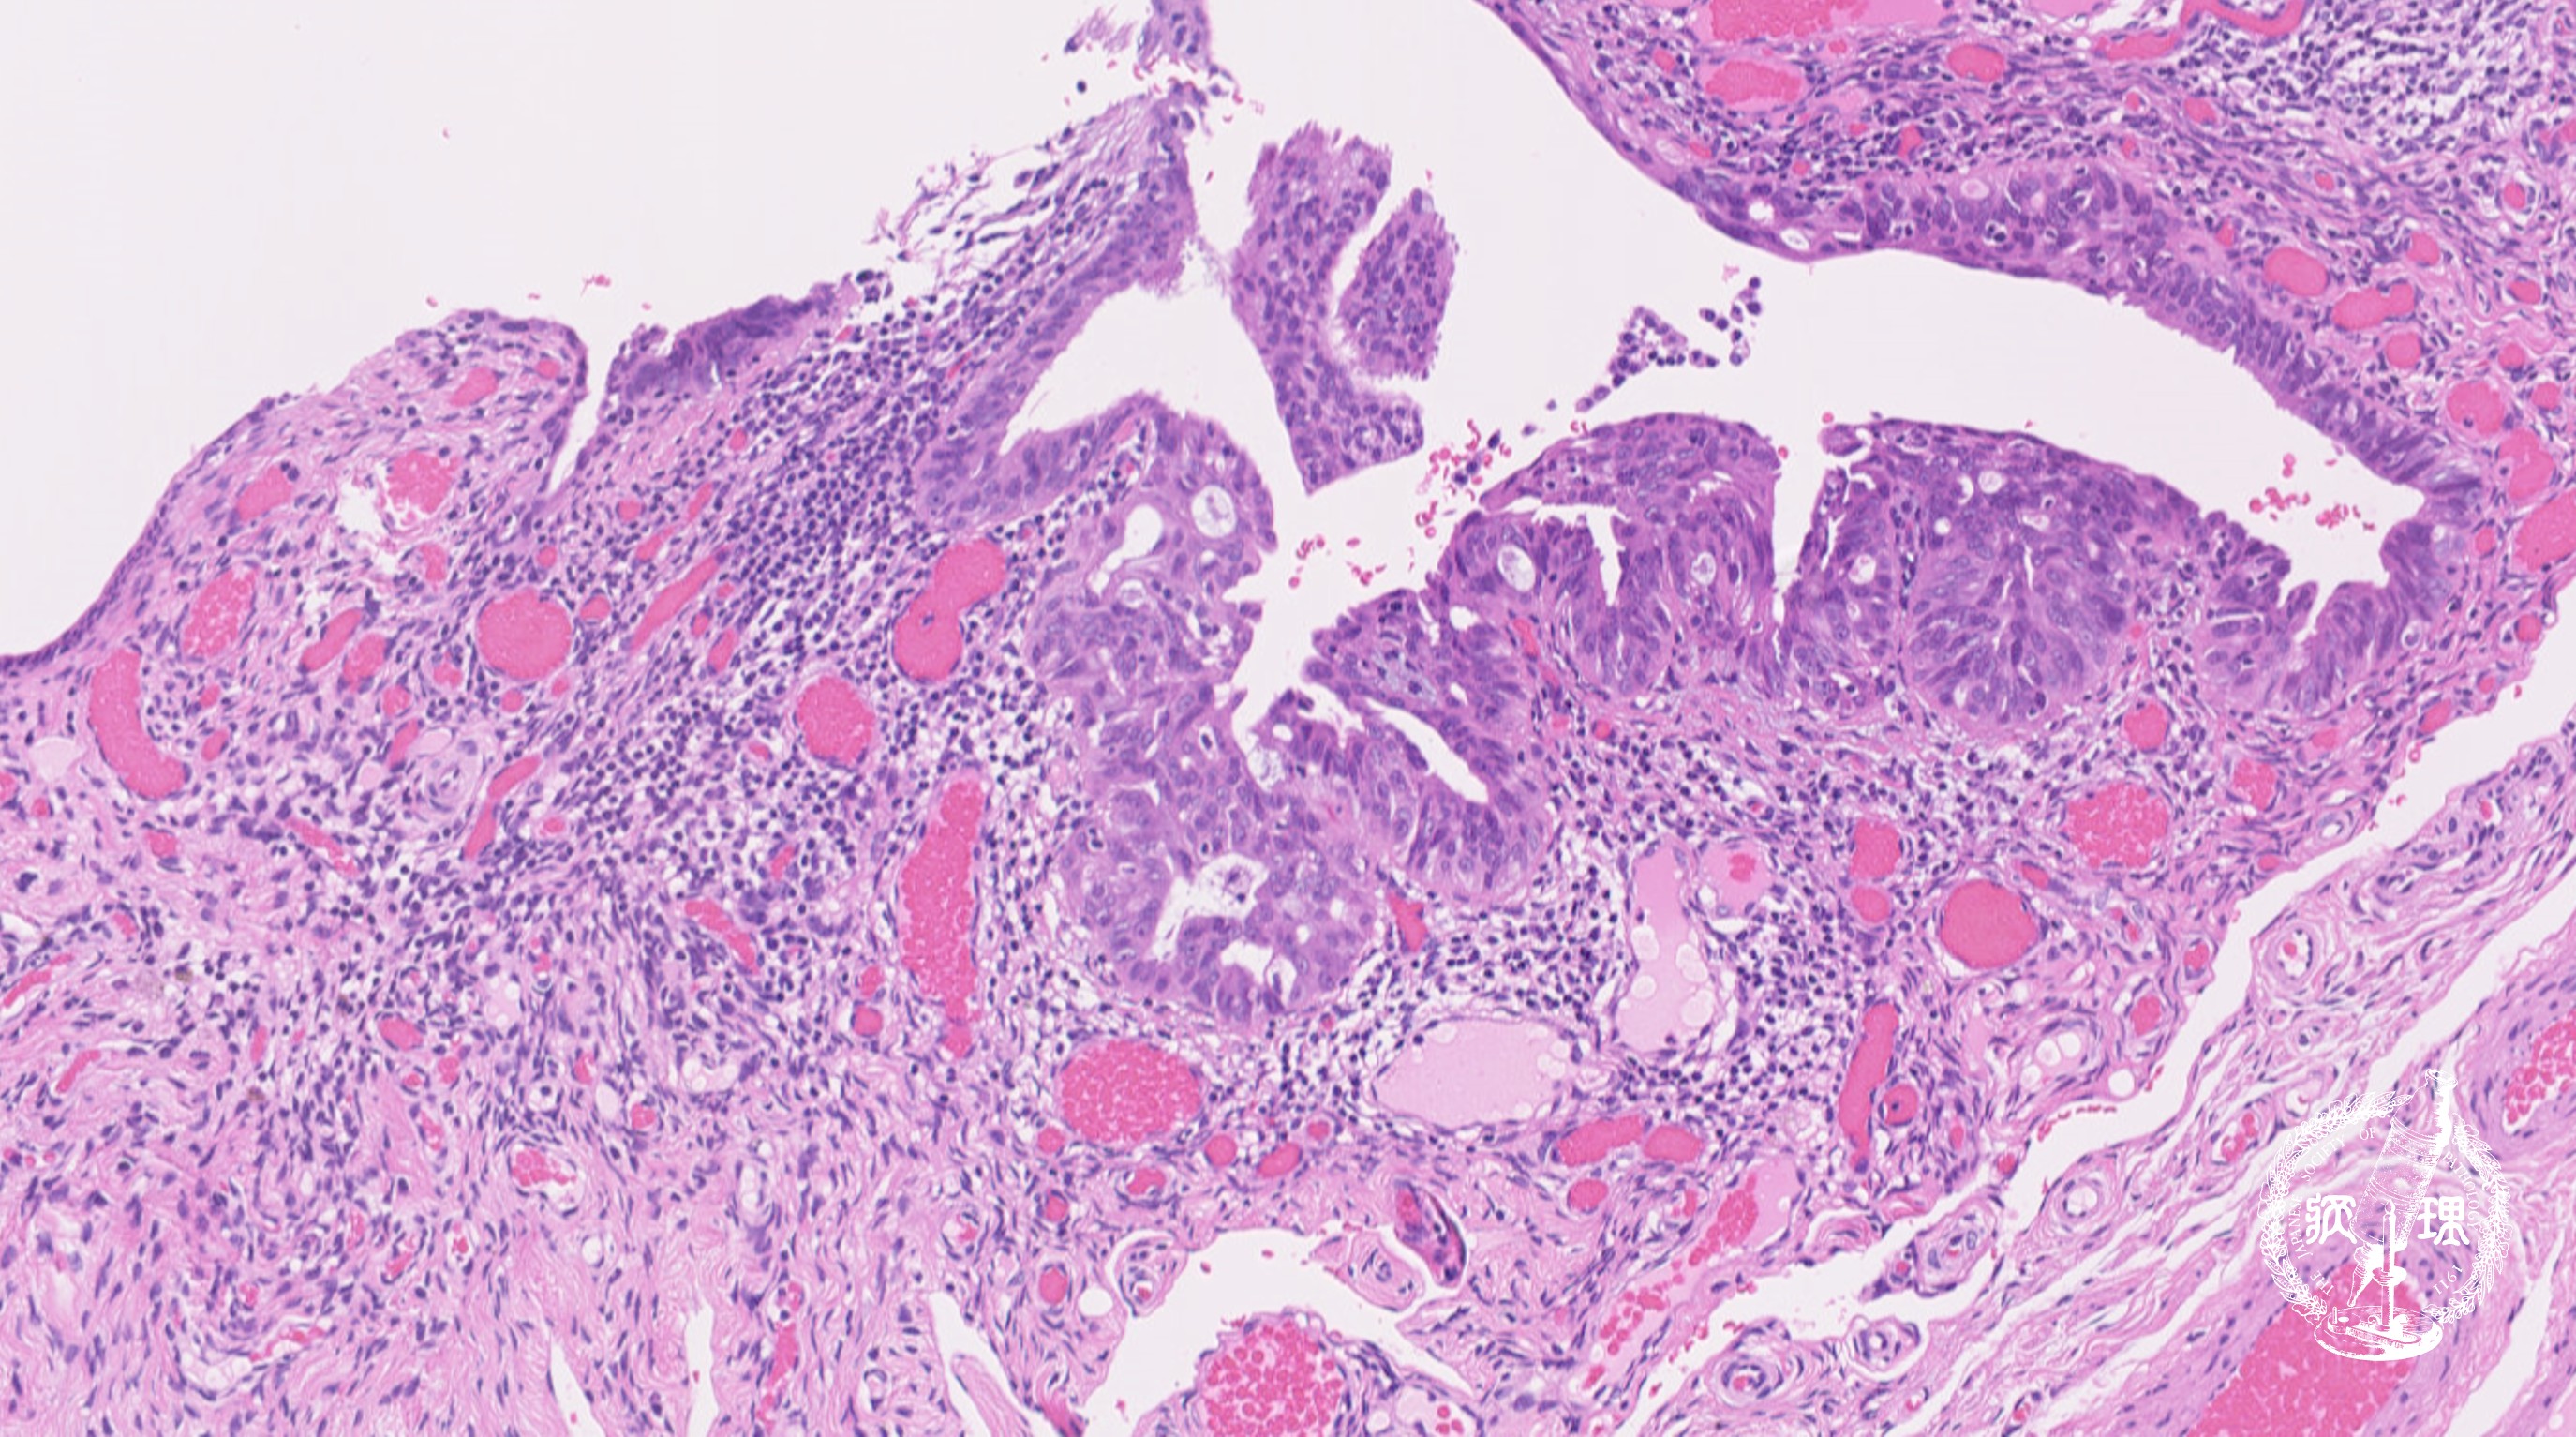

ミクロ像 (HE弱拡大):卵管采上皮。既存の卵管采上皮を置換するように、濃染腫大核を有する腫瘍細胞が密に増生している。左側には正常の卵管上皮 が残存している(矢印)。